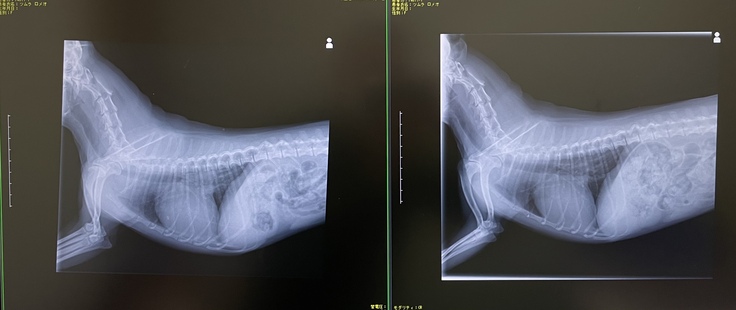

しかし、2022年10月の定期健診で前回の検査時よりも心臓肥大がかなり進行しており、肺水腫になる可能性が非常に高いとの診断を受けました。

その日より「アムロジピン錠(血圧降下薬)」を追加で投薬を開始しました。

左:2022年10月 右:2022年6月